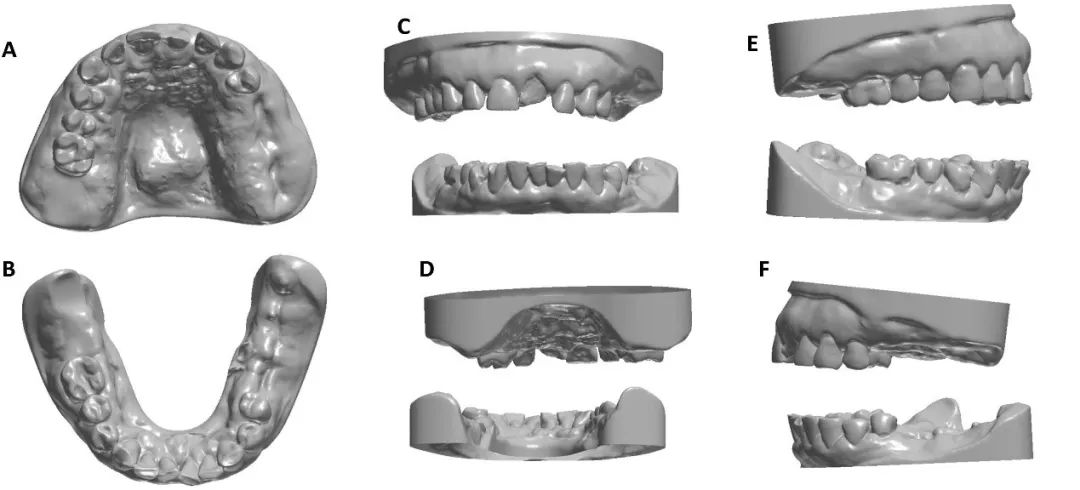

患者被转诊到牙科诊所进行放射治疗前的口腔准备。首次就诊时,进行了全面的口腔检查,拍摄了口腔内照片,并使用Trios 3口腔内扫描仪在5-10min内完成了口腔扫描。咬合扫描时使用自固化丙烯酸树脂制作的开口位夹具分离上颌和下颌。颌骨关系数字模型提交给实验室。使用3Shape Dental Software设计口腔器械。该器械覆盖了剩余牙齿的全牙合面,并接触了舌侧和颊侧牙齿表面1 mm。设计了一个从左到右的前磨牙区域的开口窗口,以促进呼吸和放射治疗期间的患者舒适度。舌板位于咬合平面下2 mm处,并向第二颌下磨牙区域向后延伸4 mm,以定位舌头。放射科医师、牙医和实验室技师在线沟通。口腔器械采用生物相容性透明丙烯酸复合材料打印制作。总打印时间为5小时,随后在405 nm紫外线光下在80℃下固化60 min。

根据适配器的安装、咬合准确性和安装时间三个参数评估了工作流效能。器械安装在咬合面后,临床评估显示其适配度与数字模型中的预计准确性相当。接下来,确定了咬合时开口2 mm的数字记录的准确性。使用定制的前夹具进行数字咬合扫描成功地复制了咬合关系。因此,这些器械可以轻松地插入到计划位置,并具有所需的开放垂直维度。器械的插入过程中的工作时间不超过15分钟。患者佩戴器械舒适,并能在被告知如何操作后的几分钟内自行插入器械。每个病例的插入就诊期间总的工作时间不超过30分钟。